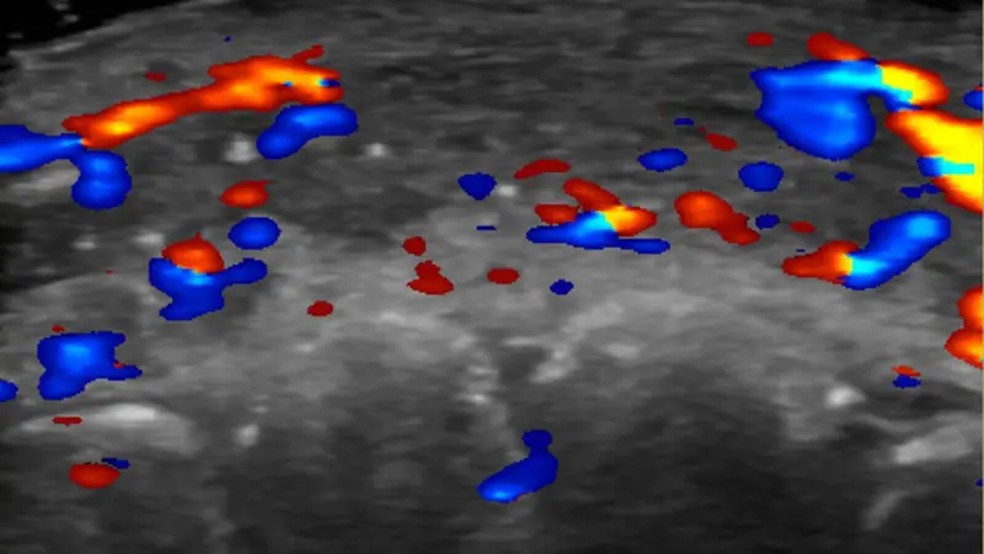

Pesquisadores usaram um ultrassom para estudar 100 casos de preenchimento que deram errado.

Em quase metade dos casos avaliados, ultrassonografias mostraram ausência de fluxo sanguíneo em vasos pequenos que conectam artérias superficiais àquelas mais profundas do rosto.

E em um terço dos pacientes, fluxo sanguíneo estava ausente nos principais vasos sanguíneos.

Um ultrassom dos lábios de um paciente mostra a ausência de fluxo sanguíneo — Foto: Rosa Sigrist e RSNA